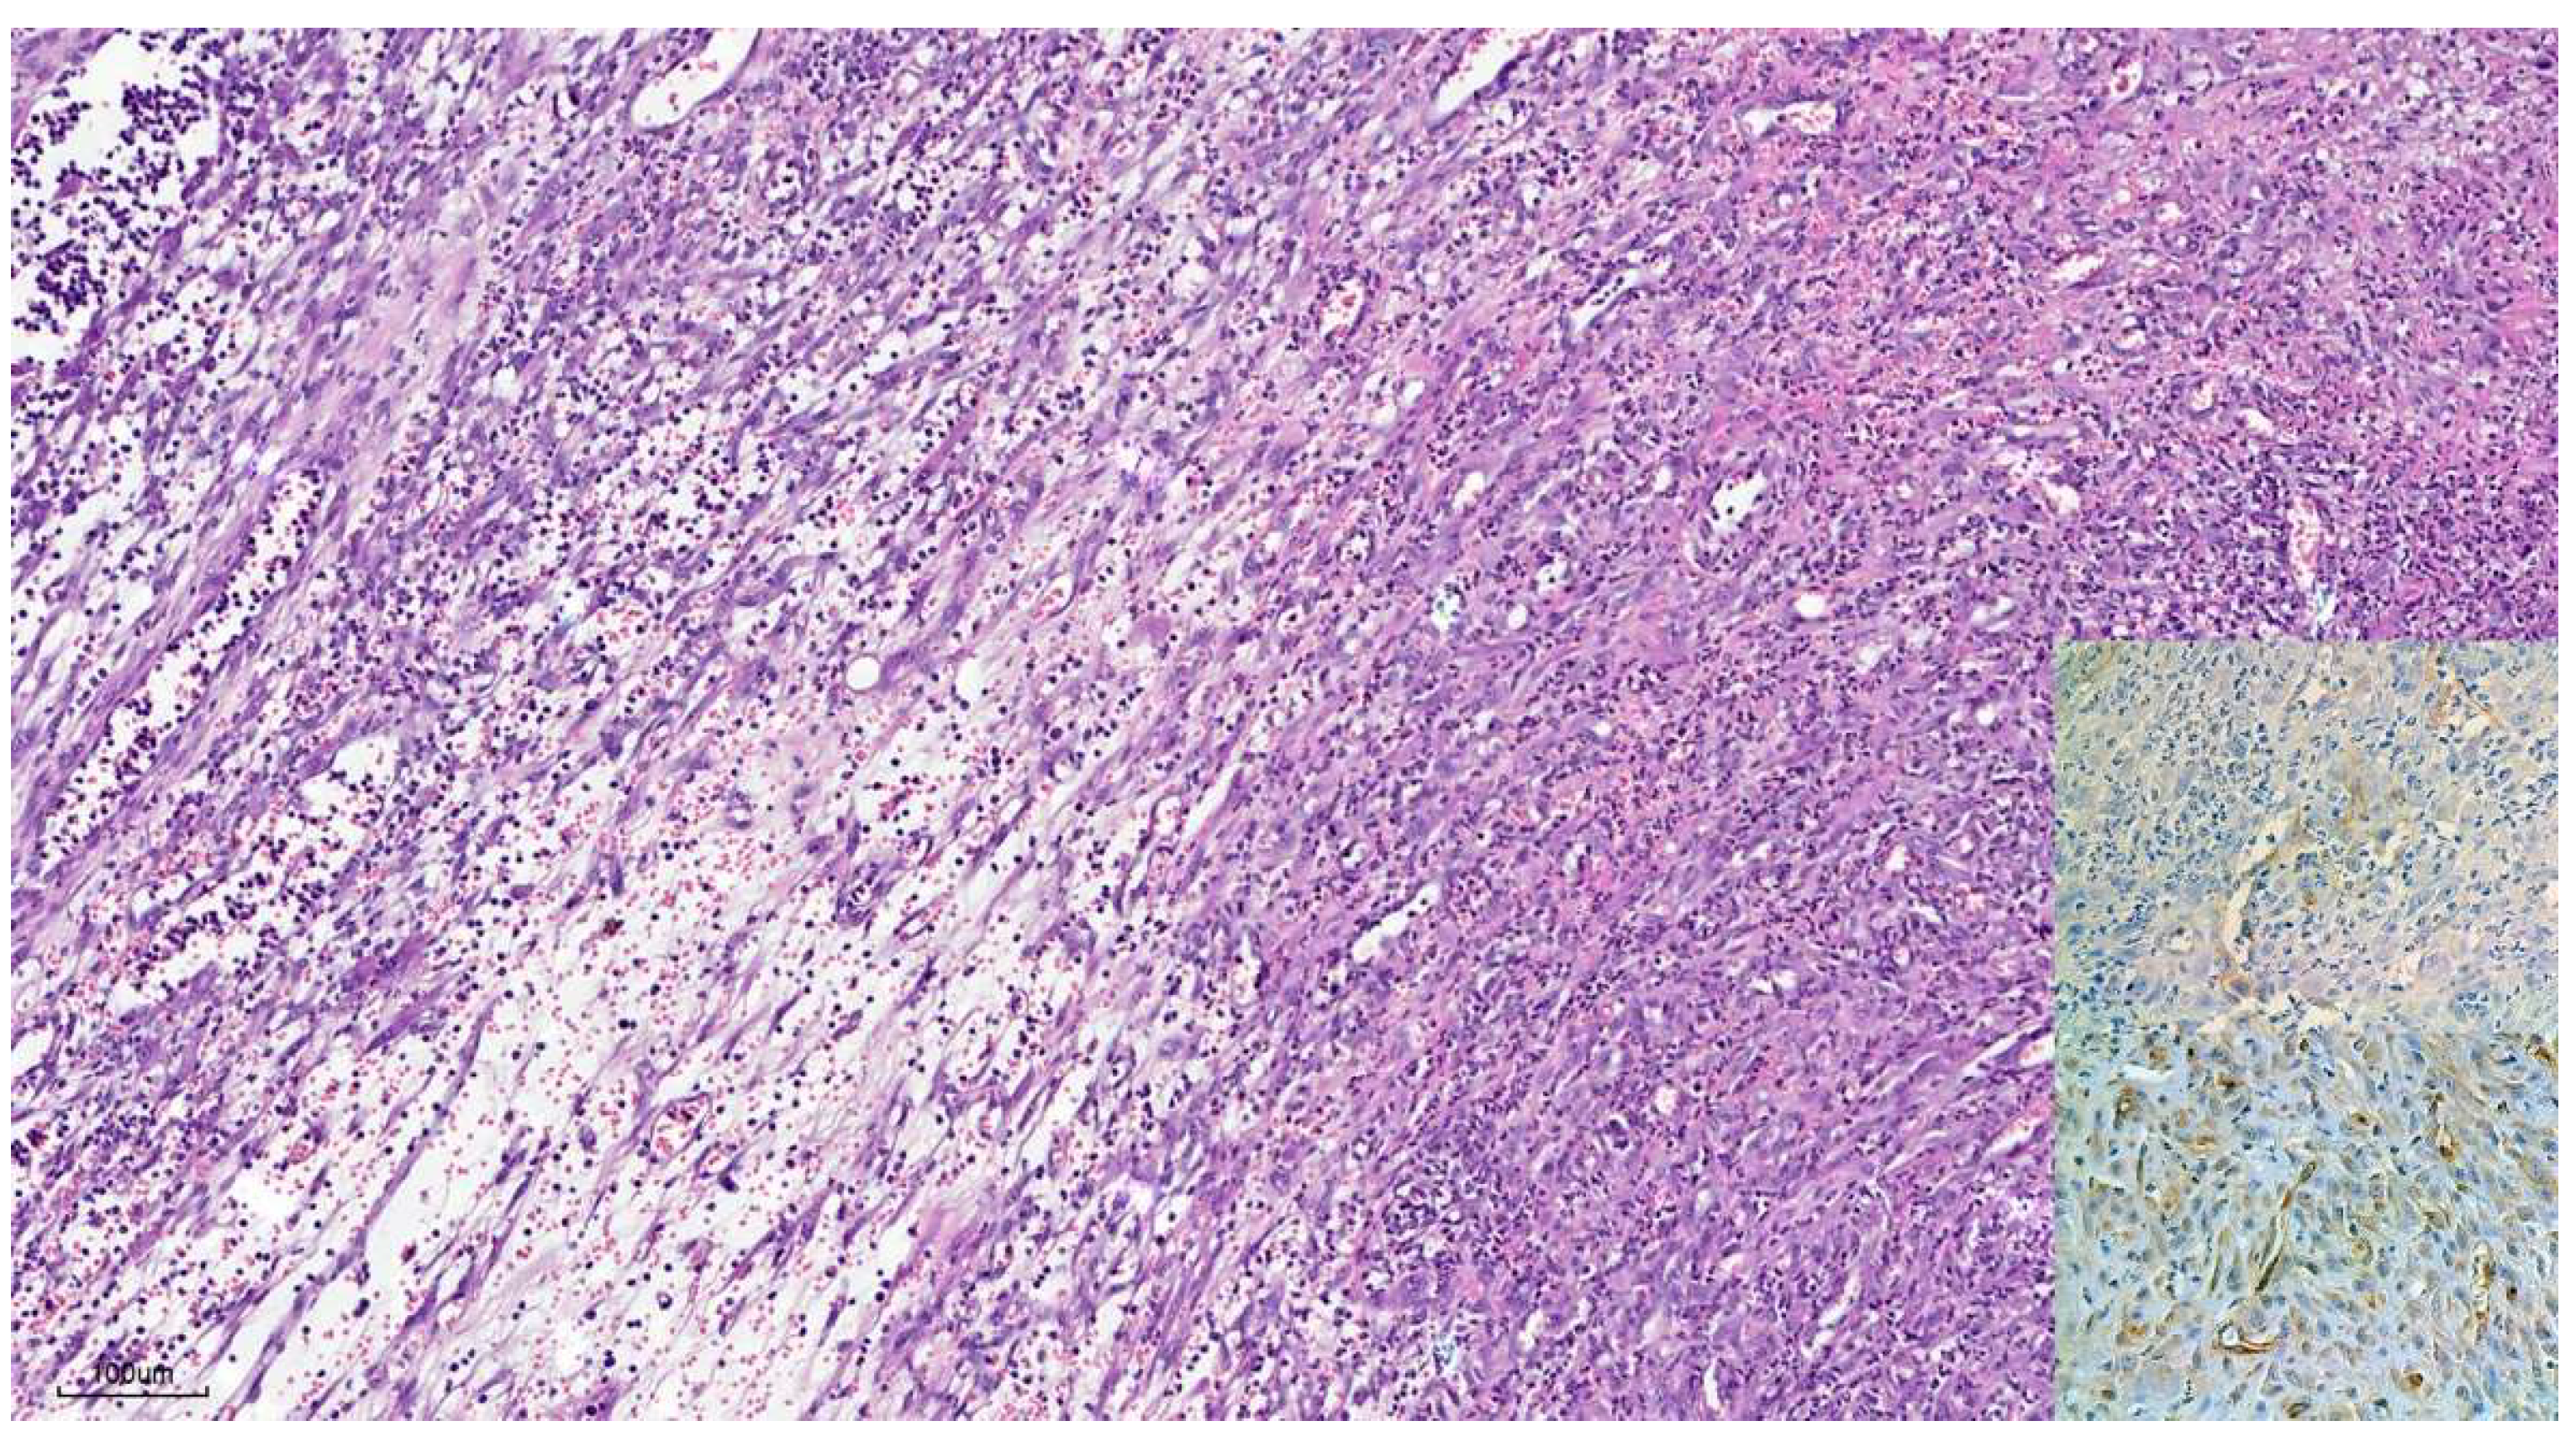

3.1.2. Histopathology

3.1.3. Immunohistochemistry

3.2.2. Histopathology

3.2.3. Immunohistochemistry